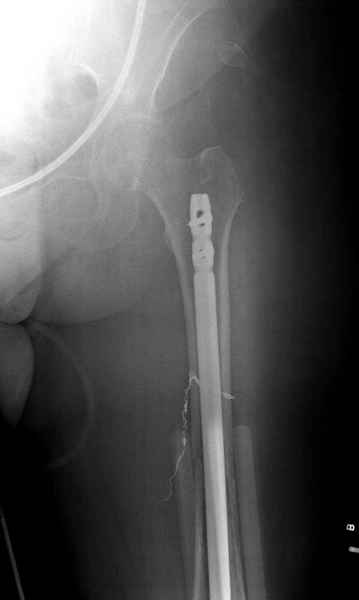

Со слов, больная ничем не болела, только последние 3 месяцев чувствовала боли в бедренной области. КТ брюшной полости подтвердил увеличенную правую почку. (5-6)

Для предупреждения кровотечения во время рассверливания, за день до операции провели эмболизацию сосудов питающий метастаз. http://radiology.rsnajnls.org/cgi/reprint/150/3/673.pdf (7-11, 12-15-16)

С минимальным рассверливанием и ретроградным методом провели остеосинтез бедра 12 мм гвоздем. (17-20)

Кровопотеря во время операции меньше 100 мл.